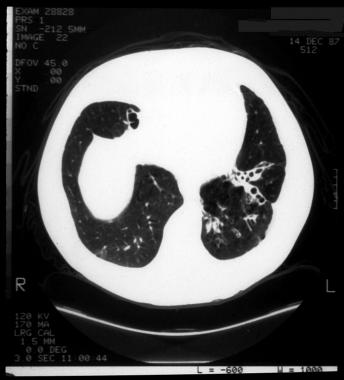

➢支气管扩张:支气管扩张是最常见的CT异常,约80%的患者可见支气管扩张,可见柱状型、曲张型和囊状型扩张。

图片

图8 显示支气管壁增厚及“轨道征”,主要在上叶